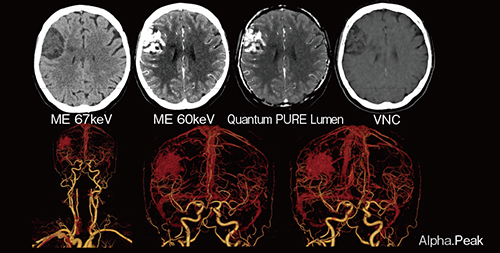

NAEOTOM Alpha.Peakの優れた時間分解能は,急性心筋疾患や不安定な臨床症状の重症患者の撮影でも高品質な画像の取得に威力を発揮する。脳内出血の症例(図8)では,CTAにて動静脈奇形が明瞭に描出され,カテーテル検査中に急性循環不全が発生した際でも,肺組織の浮腫や過灌流,基礎疾患(タコツボ心筋症)を明確に特定できた。

図8 高い時間分解能を生かした重症患者の撮影

NAEOTOM Alpha.Peakは救急部門に設置されており,心臓や小児の検査,神経内科および脳神経外科における急性出血や急性虚血性脳卒中の患者の撮影などを行っている。